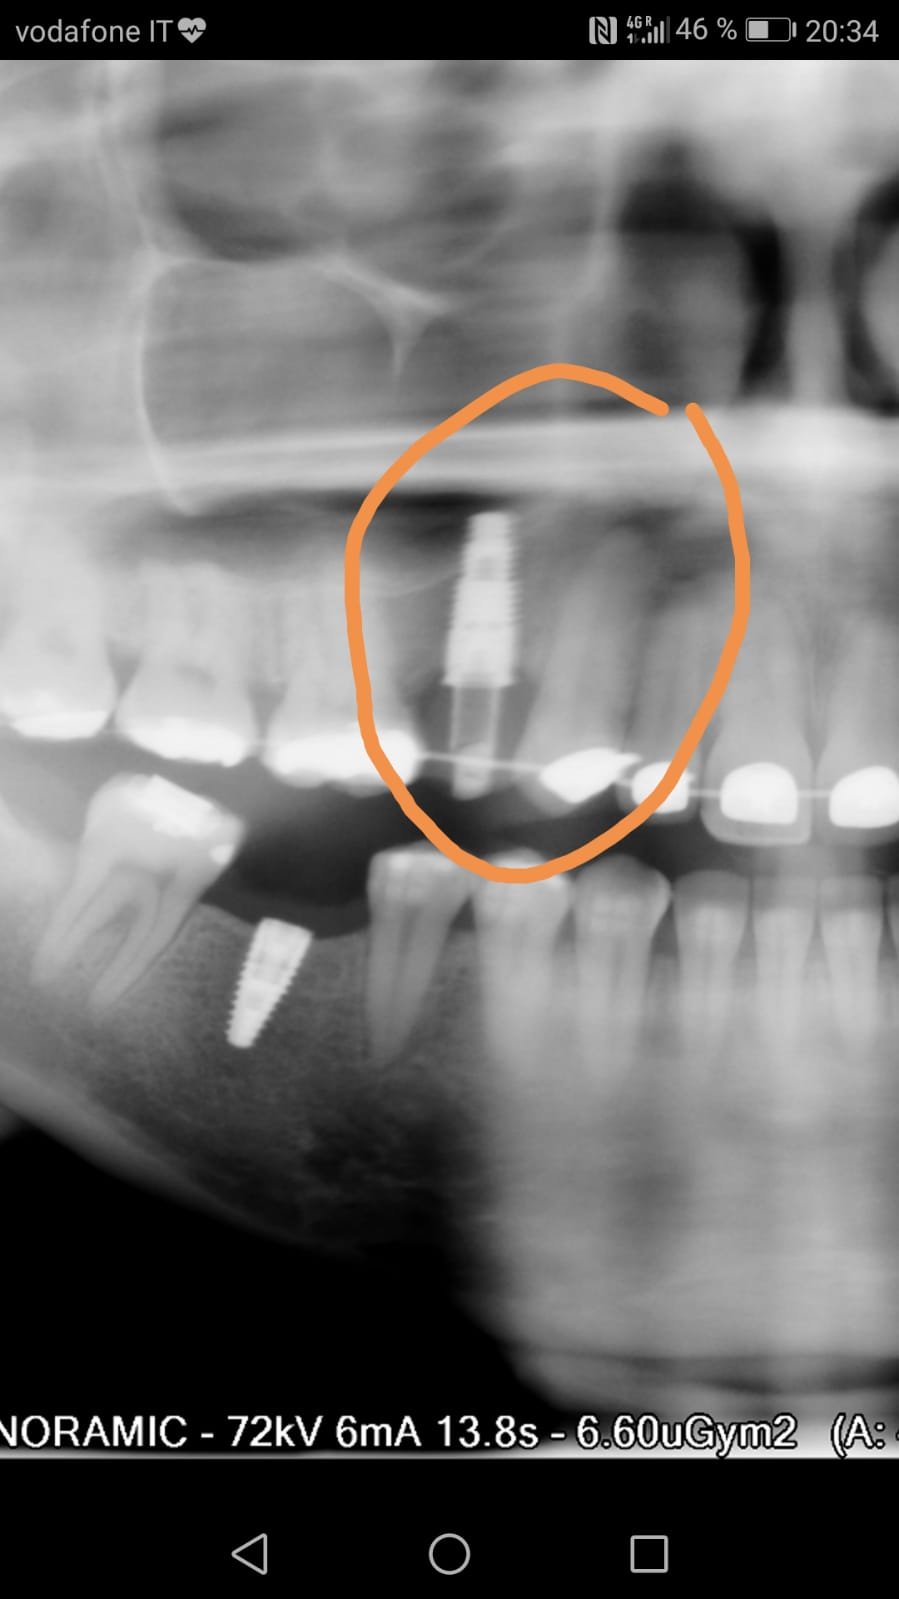

Buenas tardes: Me ha llegado este caso de un puente para cambiar pero el paciente y la clínica desconocen que implantes son. La radiografía que adjunto está tomada con [...]

Buenas tardes. quería saber cual era el implante situado a nivel del 16. Muchas gracias.